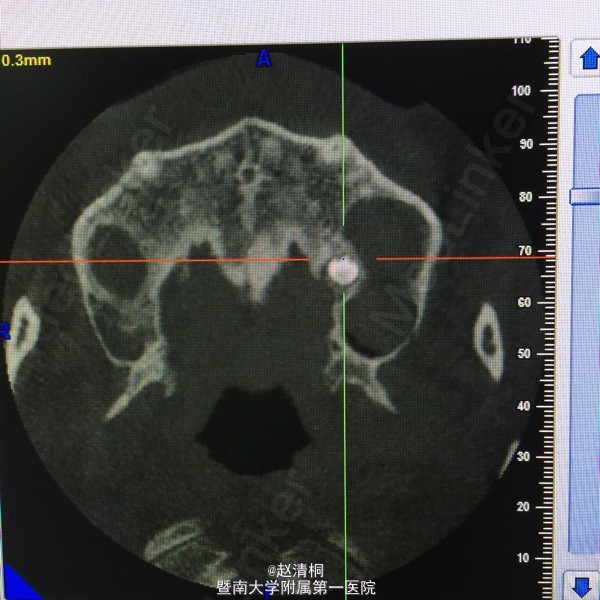

CBCT显示只有3mm骨量,上颌窦内侧壁有一多生牙,没有CT,这种病例不敢种的。